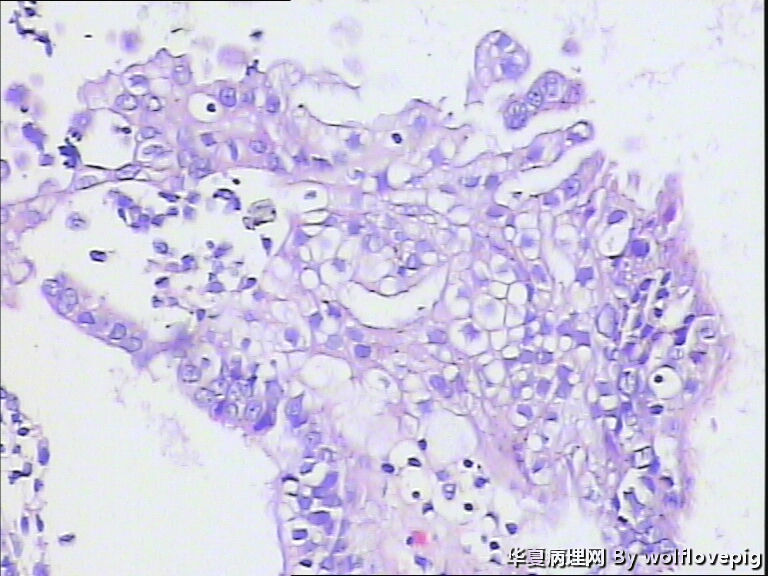

40y,阴道不规则流血10+天

流血期子宫内膜,这些变化都是化生,不怕

分泌期宫内膜伴嗜酸细胞化生

乳头状化生,嗜酸细胞化生,透明细胞化生

分泌期宫内膜伴嗜酸细胞、乳头状化生

医源性改变(药物等)。

是一种化生性改变,问题不大。